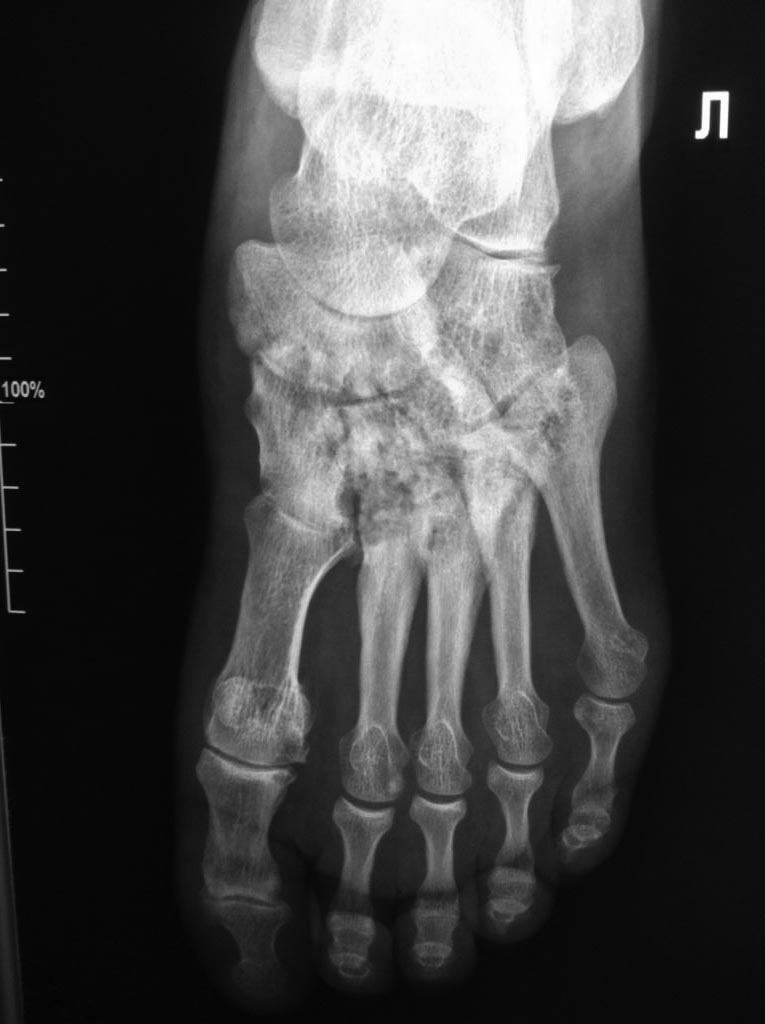

[Ortho] Асептический некроз костей среднего отдела стоп.

Доброго времени суток. Обратился пациент, 62 года, бытовые и трудовые

условия в данное время не отягощены и не были никогда тяжелыми, без

вредных привычек, со слов оперативных вмешательств не было, курсов

гормональной терапии не получал, периодически принимает лекарственные

препараты от арт. гипертензии. Без видимых причин около 1 года назад

появились боли в стопах при ходьбе и нагрузке, в связи с чем обратился к

ортопеду.

Лаб исследования: Ревмофактор, С-реакт. белок, АЦЦП, Мочевая кислота и

др. в пределах возрастной нормы. Хотелось бы услышать мнения. Заранее

благодарен.

Вложение не в текстовом формате было извлечено…

Имя     : IMG_5005.jpg

Тип     : image/jpeg

Размер  : 86017 байтов

Описание: отсутствует

Url     : http://weborto.net:8080/pipermail/ortho/attachments/20141117/cf23b1b3/attachment-0006.jpg